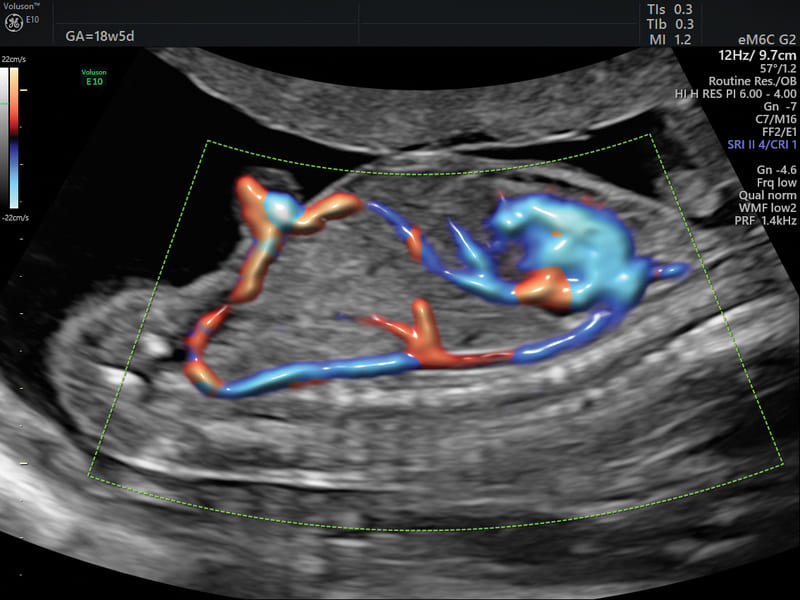

Radiantflow: algoritmo avanzato che permette di ottenere informazione di altezza e profondità del Color Doppler, Power Doppler e HDFlow™ con visualizzazione in tempo reale 3D Like.

SlowflowHD™: software per lo studio della vascolarizzazione che grazie all’altissima sensibilità è in grado di sopprimere i movimenti a bassa frequenza preservando le informazioni sul flusso.

Slowflow 3D: È possibile abbinare le varie tecnologie Volume Ultrasound integrate nella piattaforma per uno studio approfondito delle strutture vascolari del cervello fetale, dei vasi addominali e in applicazioni ginecologiche, quali lo studio dell’adenomiosi tramite Slowflow 3D.